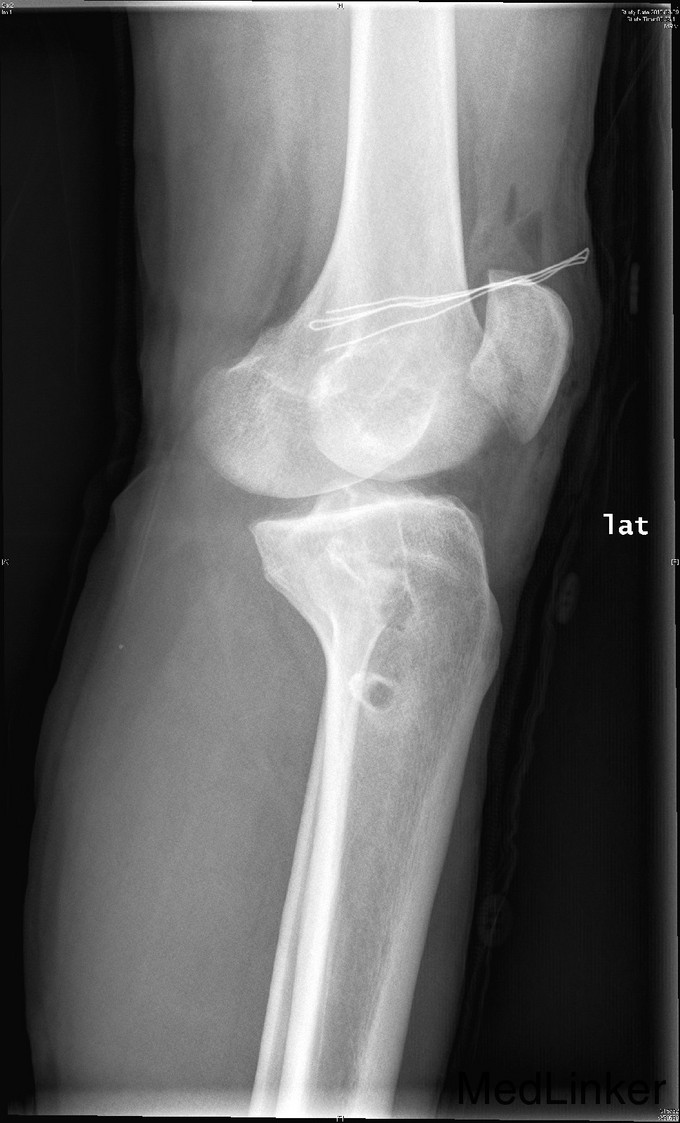

主诉:左膝前交叉韧带重建术后,要求取内固定 。 现病史:患者9年前运动时扭伤左膝关节,后出现左膝不稳、左下肢乏力。患者当时来我院就诊,诊断左膝前交叉韧带损伤,行左膝前交叉韧带自体重建术。患者自觉术后恢复良好,未规律行康复锻炼。2年前患者自觉左膝行走时偶有交锁伴疼痛。今患者为取左下肢内固定物来我院就诊。

查体:右下肢、双上肢肌力及活动度正常。左股四头肌萎缩,肌力V-级。左膝关节无明显肿胀,关节ROM尚正常,关节过伸过屈时无疼痛。髌骨活动度正常,髌周无压痛。浮髌试验(-),压磨髌(-)。麦氏征(+)。关节间隙压痛(+)。ADT(+-),Lachman征(+-),侧方应力实验(-)。双下肢无明显感觉异常。 左膝X线示:左膝术后改变。 注:患者因体内内固定无法进行核磁共振检查,这也是患者强烈要求取出内固定的原因。

诊断:左膝前交叉韧带重建术后,左膝半月板损伤。 治疗:左膝内固定取出术+左膝关节镜下探查+左膝前交叉韧带皱缩+内侧半月板成形术